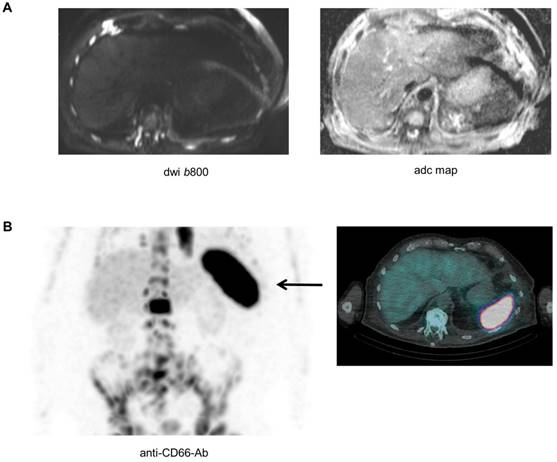

Biopsying the spleen is risky and barely possible, and as a result it is difficult to directly investigate the pathological features of the spleen in patients with absence of the signal. Yet, as recently shown, a combination of modalities could improve our understanding of the biology underlying imaging phenomena [11]. A late stage relapsed patient with high tumor burden (>80%BMPC), a ferritin value of 292 µg/l (reference 30-400 µg/l), and absence of spleen signal on DW-MRI also underwent Tc-99m labelled anti-CD66 antibody scintigraphy for evaluation of a targeted radiotherapy approach. The scintigraphy revealed extensive CD66 expression in the spleen (Figure 4). CD66 is expressed on mature myeloid cells including promyelocytes and granulocytes [14], and was recently used as a marker for extramedullary hematopoiesis (EMH) in a patient with myelofibrosis [15]. Thus, our preliminary observation suggests that EMH in the spleen is a factor that modifies the DW-MRI signal of this organ.

Figure 4

The asplenia phenomenon and extramedullary hematopoiesis. A patient with advanced MM and absence of spleen signal on DW-MRI also underwent Tc-99m labelled anti-CD66 antibody scintigraphy. In (A) the b800 DWI and ADC maps are shown. In (B) results of the Tc-99m labelled anti-CD66 antibody scintigraphy are depicted.

While our observations strongly support the hypothesis, that the spleen signal is associated with a high BMPC involvement, the biological mechanism for this phenomenon remains largely elusive as it would require spleen biopsies. Yet, using anti-CD66 antibody scintigraphy in one patient with absence of spleen signal on DW-MRI, we observed a strong CD66 signal in the spleen, suggesting EMH to underlie the asplenia phenomenon in this patient. In principle, presence of EMH in patients with an obliterative BMPC involvement is not an unexpected finding, as MM cells crowd out other hematopoietic cells in the BM. In line, EMH in NDMM has previously been described by Seo et al., who performed a biopsy of a paravertebral mass with mild FDG uptake and detected EMH in this mass [19]. EMH in MM patients was also reported by Baldane et al. [20] and Palma JA et al. [21].